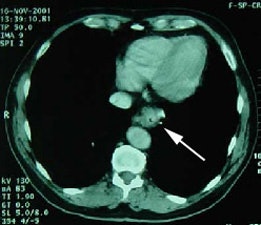

Metastatic esophageal carcinoma: The patient presented for evaluation of a pulmonary nodule. PET revealed tracer uptake in the nodule (black arrow), as well as in an esophageal mass (red arrow), para-esophageal adenopathy, and liver metastases (blue arrows). |